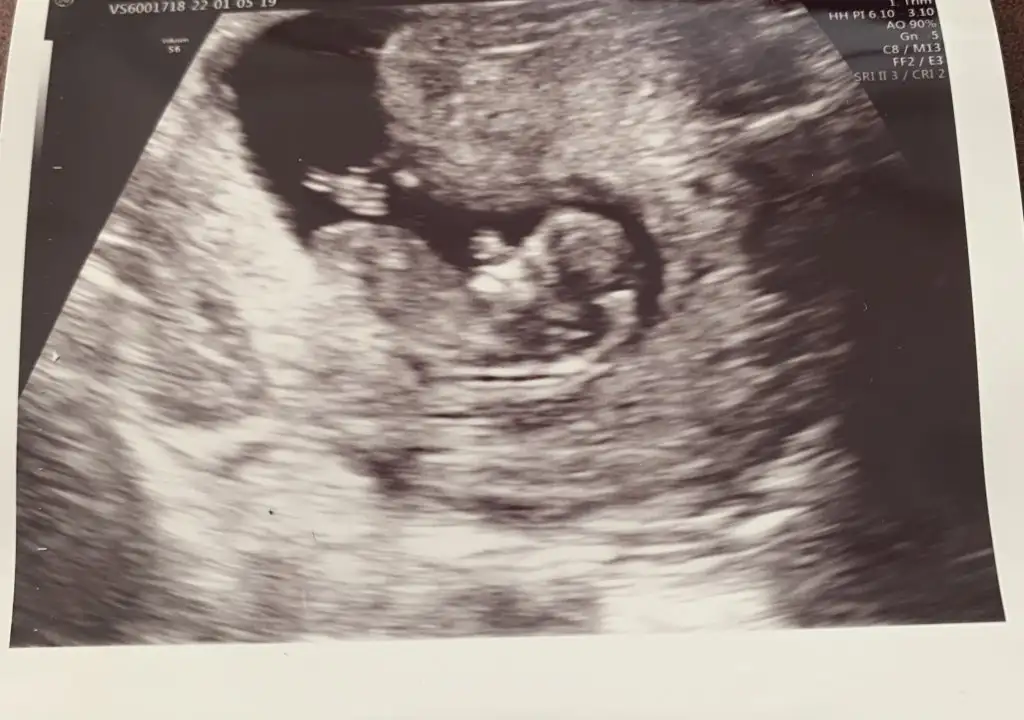

selam kızlar 13+1 doktor henüz bir tahminde bulunmadı lütfen anlıyorsanız görüntülere bakar mısınız